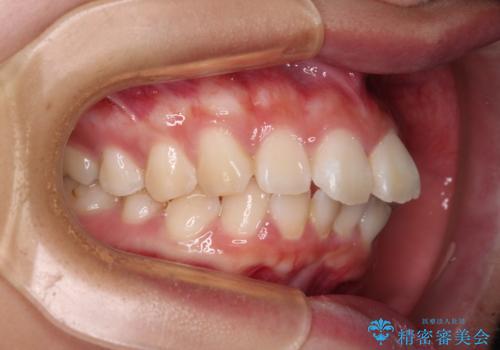

- 前歯部のデコボコと口元が出ているのが気になるとのことで来院された患者様です。

口元の突出感の解消と、このままデコボコを解消するとさらに出っ歯傾向になってしまうことを考慮し、上下左右の小臼歯を抜歯しクリアブラケットにて矯正していくこととしました。

舌突出癖を改善するトレーニングを一生懸命やっていただいたおかげで2年以内に治療を終えることができました。